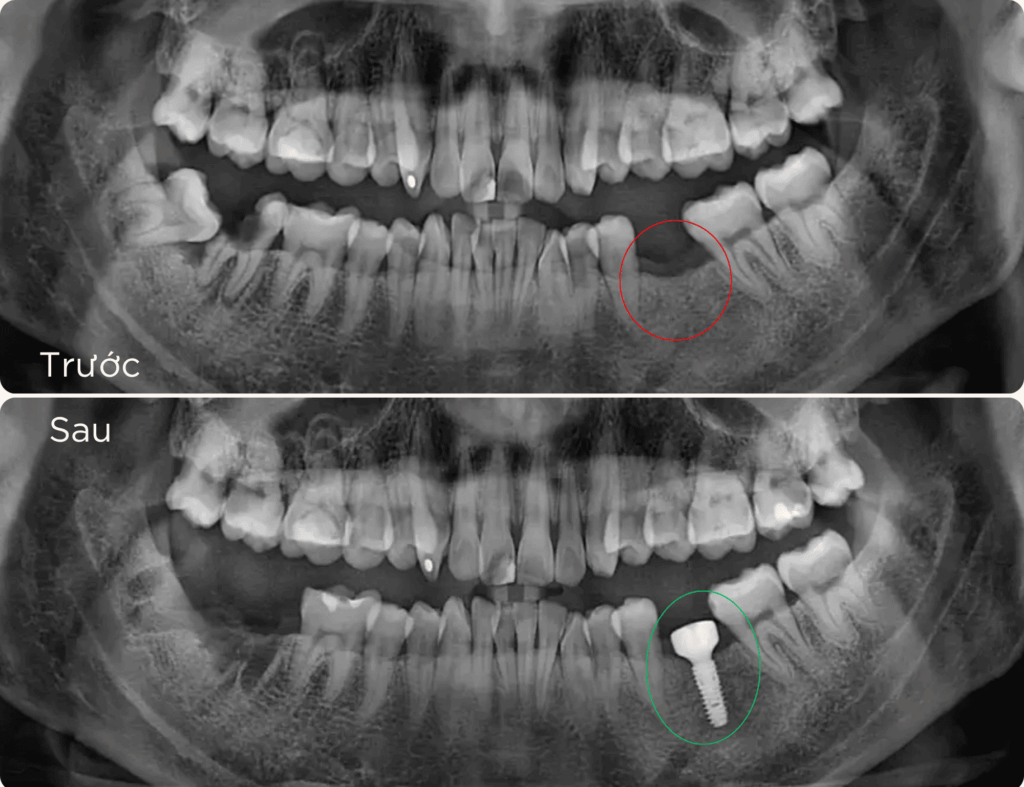

là phương pháp phục hồi răng mất tiên tiến, sử dụng trụ chụ chân răng nhân tạo – Implant từ titanium cấy vào xương hàm để thay thế chân răng đã mất. Sau đó, một mão răng sứ được gắn lên trụ, tạo ra chiếc răng mới với hình dáng và chức năng giống như răng thật.